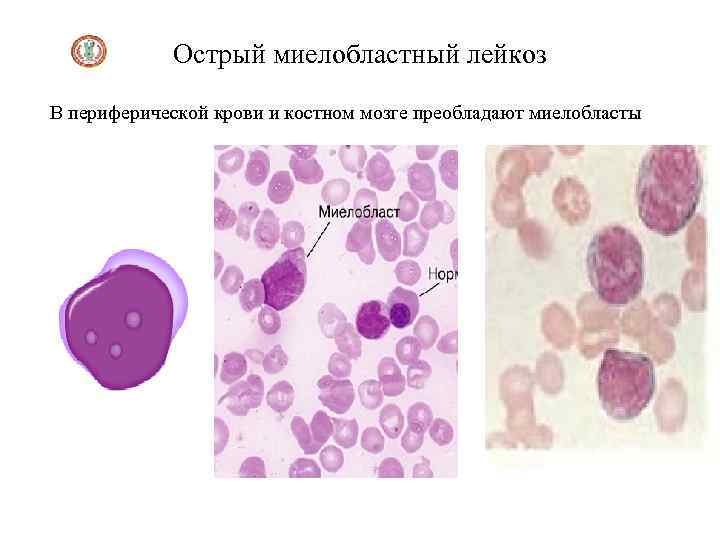

Острый миелобластный лейкоз В периферической крови и костном мозге преобладают миелобласты

Острый миелобластный лейкоз